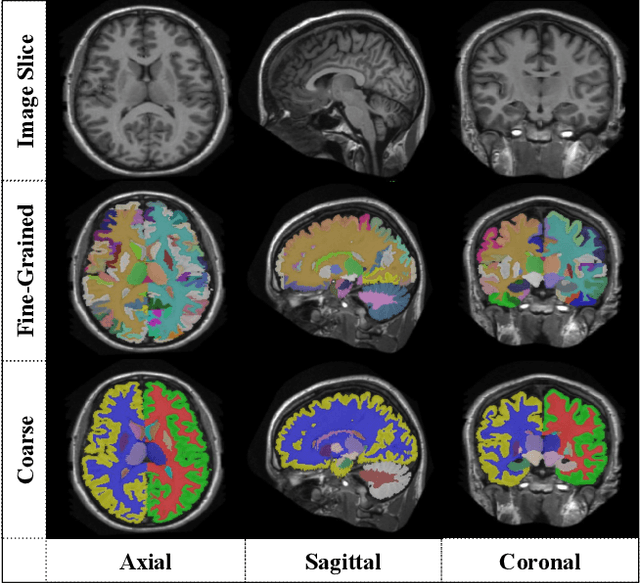

Automatic segmentation of fine-grained brain structures remains a challenging task. Current segmentation methods mainly utilize 2D and 3D deep neural networks. The 2D networks take image slices as input to produce coarse segmentation in less processing time, whereas the 3D networks take the whole image volumes to generated fine-detailed segmentation with more computational burden. In order to obtain accurate fine-grained segmentation efficiently, in this paper, we propose an end-to-end Feature-Fused Context-Encoding Network for brain structure segmentation from MR (magnetic resonance) images. Our model is implemented based on a 2D convolutional backbone, which integrates a 2D encoding module to acquire planar image features and a spatial encoding module to extract spatial context information. A global context encoding module is further introduced to capture global context semantics from the fused 2D encoding and spatial features. The proposed network aims to fully leverage the global anatomical prior knowledge learned from context semantics, which is represented by a structure-aware attention factor to recalibrate the outputs of the network. In this way, the network is guaranteed to be aware of the class-dependent feature maps to facilitate the segmentation. We evaluate our model on 2012 Brain Multi-Atlas Labelling Challenge dataset for 134 fine-grained structure segmentation. Besides, we validate our network on 27 coarse structure segmentation tasks. Experimental results have demonstrated that our model can achieve improved performance compared with the state-of-the-art approaches.